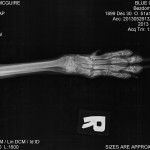

Today our new boy we have named Ricky arrived at our clinic. His tests so far show a crush type injury to the bones in his front foot, with the injury itself infected, so he has a high fever and raised blood cell counts, indicating he is fighting an infection. He is therefore having is treatment to wash the wound twice a day with an immobilization bandage each time until the bones heal.